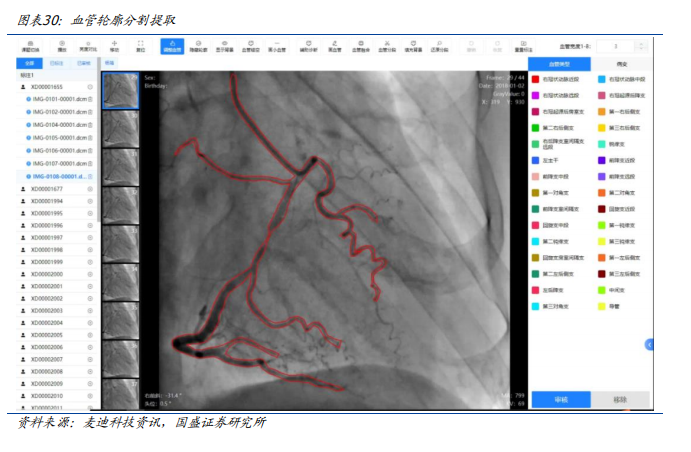

早在2023年,由麦迪科技研发的心血管医学影像人工智能科研平台在复旦大学附属中山医院落地。该项目是基于复旦大学附属中山医院在心血管疾病方向的学科集群优势,研发的一款与影像大数据库连接的“一站式”心血管医学影像人工智能科研平台,实现科研影像数据的快速收集,以及人工智能科研所需的标注、清洗、存储、训练和验证等功能。

心血管医学影像人工智能科研平台是基于计算机视觉网络模型的人工智能技术框架作为AI基础服务层,打造心血管人工智能影像分析平台为临床提供辅助诊疗服务。包含冠脉造影、血管内超声及CT血管造影等心血管疾病影像检测智能分析功能。通过对冠脉造影血管轮廓智能提取可以快速定位血管狭窄,完成血管狭窄分析,实现狭窄血管重建与定量测算,分析计算狭窄的功能学指标参数;同时还提供手术支架建议,便于快速制定介入手术方案。通过血管内超声影像分析可以快速完成血管内超声图像分析,实现斑块定位与测算,便于快速制定后续的治疗方案。